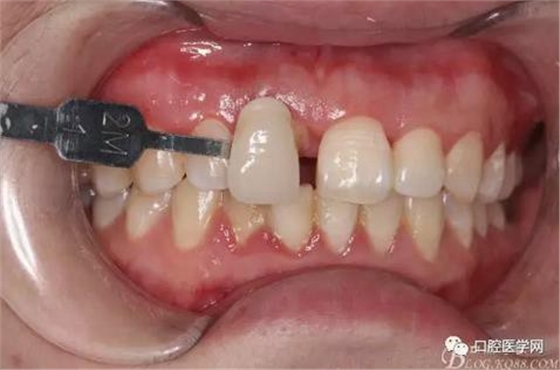

比色

牙冠延長術(shù)后6周復(fù)診牙齦齦緣形態(tài)恢復(fù)良好,齦乳頭有些欠缺,患者著急永久修復(fù)。